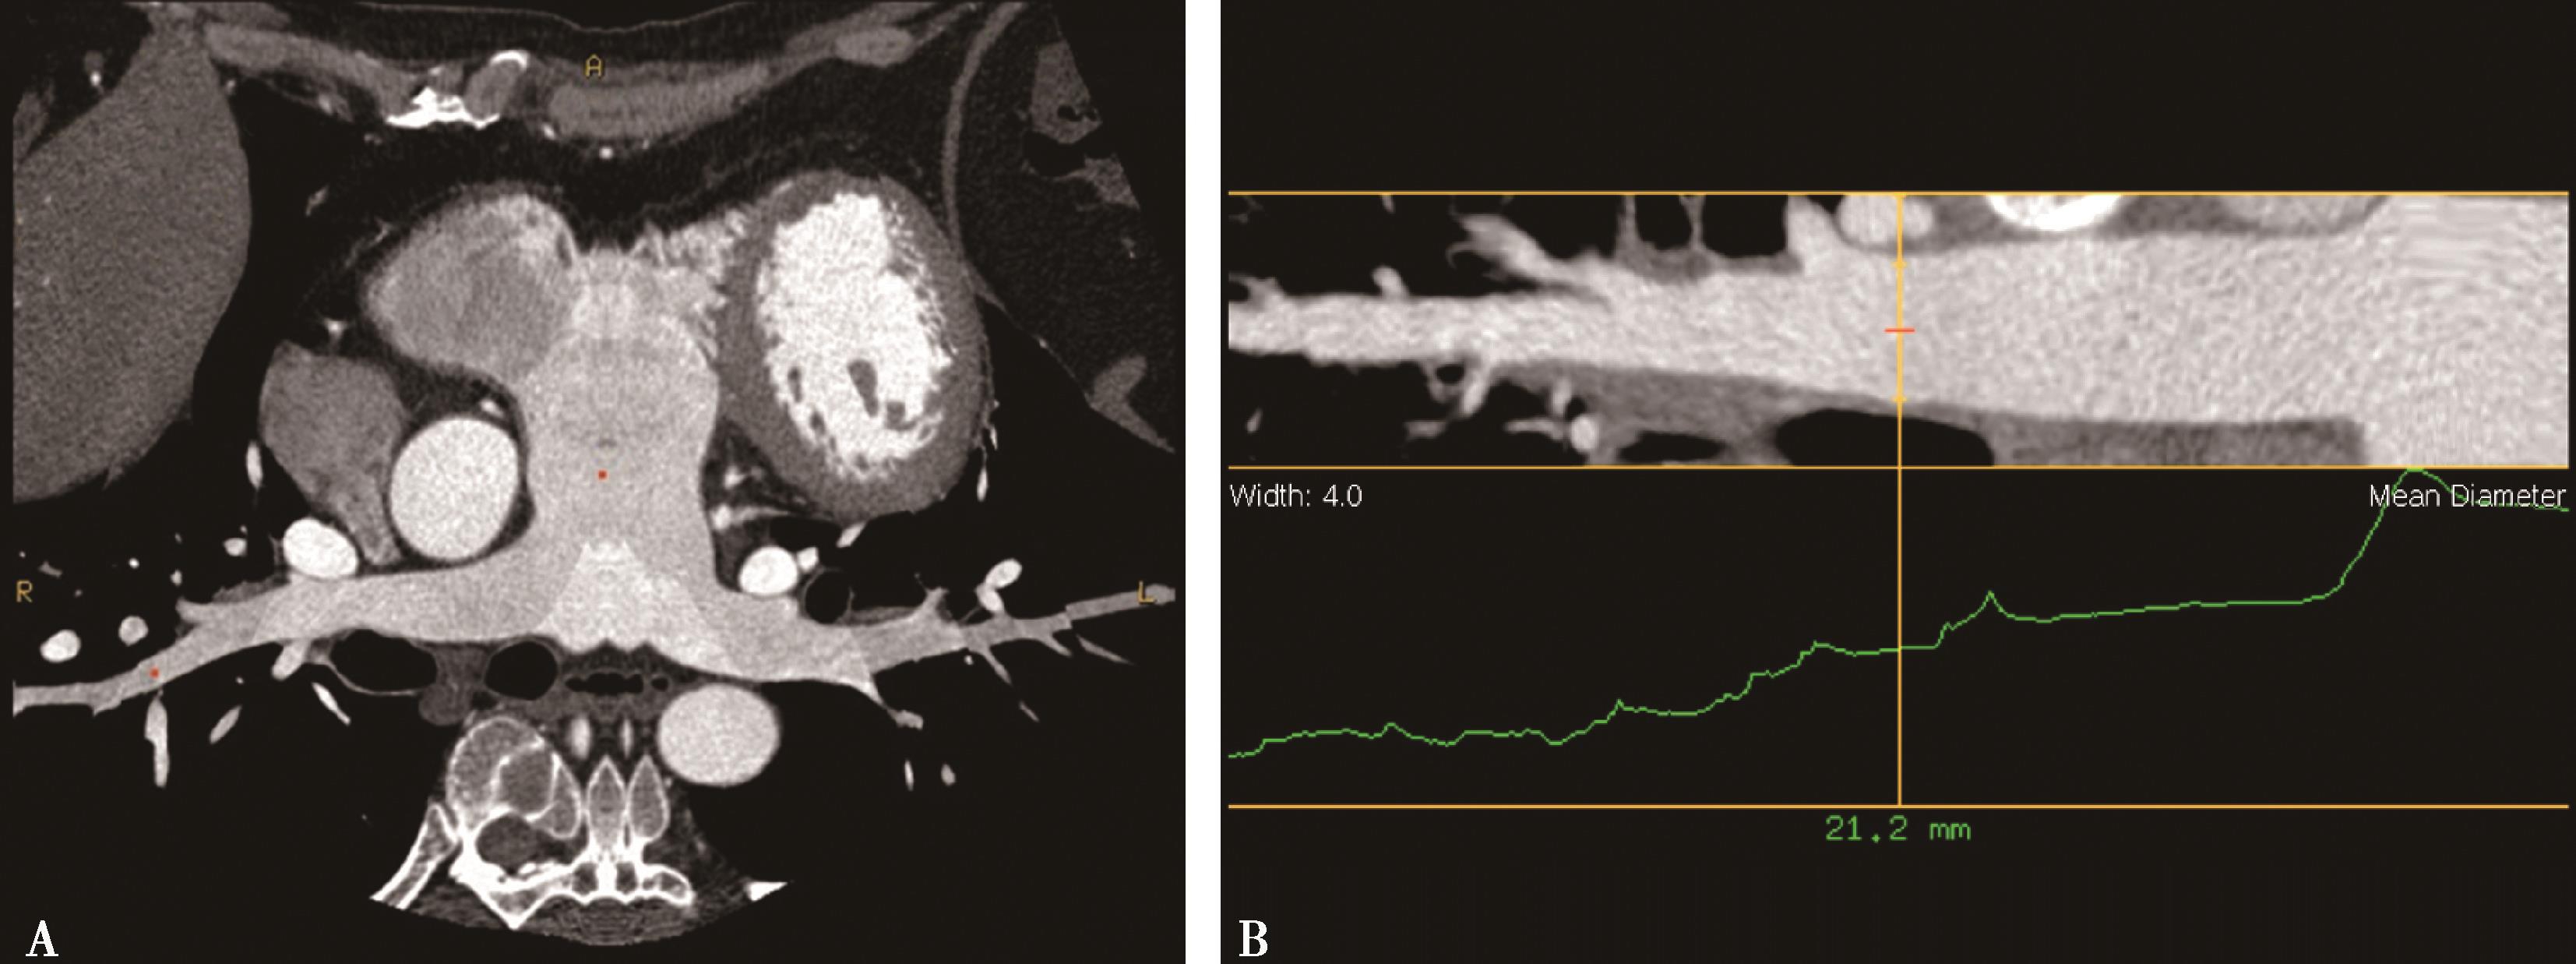

(6)获得单能量70keV下CTA图像,即碘基物质图像(iodine-based material decomposition images)(图 8-1-6)。

图8-1-6 右肺下叶外基底段栓塞;能谱成像得到肺碘基物质图,反映栓塞分布、梗阻呈低灌注、程度

(1)提高了肺栓塞检出的敏感度(提高20%),检出段-亚分段及隐性栓塞。

(2)实现肺灌注功能诊断检查,碘基物质图对定量分析提供更为科学的依据。